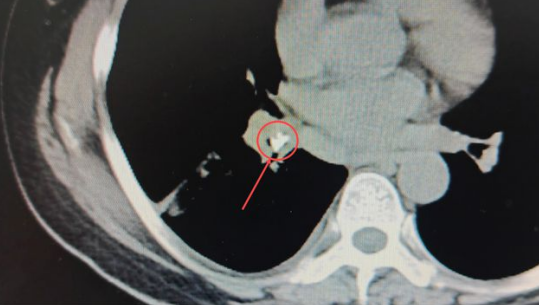

在CT影像中能夠很清晰地發(fā)現(xiàn):患者右肺葉已經(jīng)出現(xiàn)大面積實變[1],形成“白肺”(正常的肺葉組織在CT影像中呈黑色),在右肺基底段的一截支氣管中,有一個類似鈣化的“亮點”。醫(yī)生們進一步仔細查看,發(fā)現(xiàn)這個亮度極高的異物顯示出的密度與骨骼的密度相近。

安女士肺部CT影像中極不尋常的“亮點”,馬上成為醫(yī)生們高度關(guān)注的疑點,這也進一步印證了礦總呼吸科專家做出的推斷:果然有異常的東西滯留肺內(nèi),才導致患者如此嚴重的咳喘癥狀。

▼紅圈內(nèi)即卡在肺內(nèi)的異物